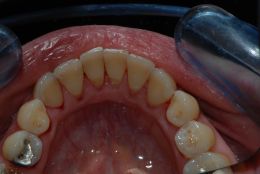

E' ben visibile l'infiammazione gengivale e l'accumulo di tartaro pigmentato da nicotina nella visione linguale.